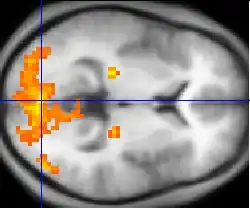

PET, fMRI, fNIRS and fUS can measure localized changes in cerebral blood flow related to neural activity. These changes are referred to as activations. Regions of the brain which are activated when a subject performs a particular task may play a role in the neural computations which contribute to the behaviour. For instance, widespread activation of the occipital lobe is typically seen in tasks which involve visual stimulation (compared with tasks that do not). This part of the brain receives signals from the retina and is believed to play a role in visual perception.